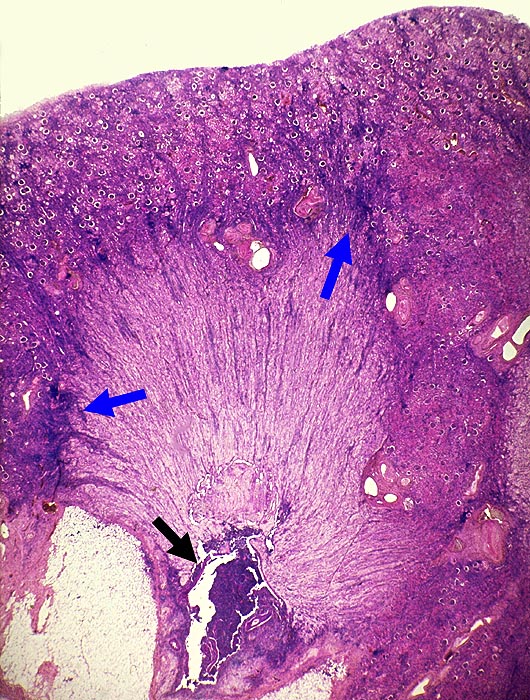

AP/ Analgetikanephropathie

Analgetikanephropathie

Niere

Morphologie

Pathologischer Befund